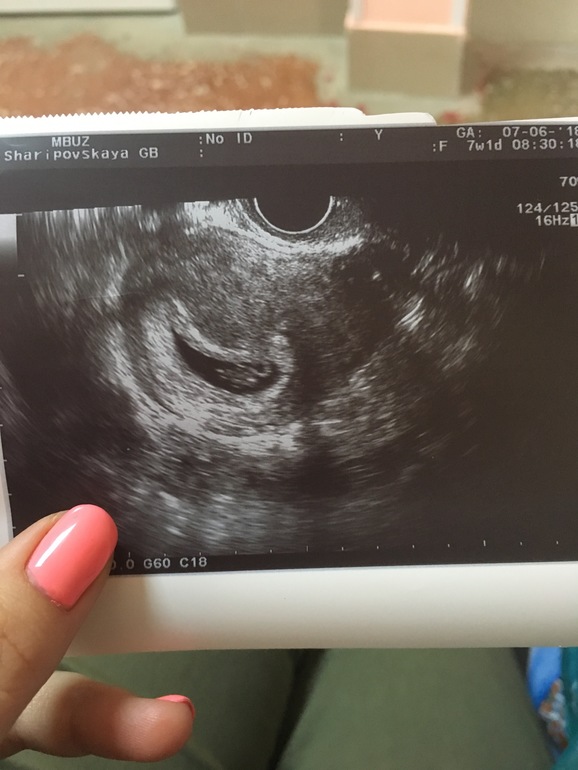

Всё о нашей беременностиВсем привет! Вчера ходила к врачу, поставили гипертонус . Кто понимает в Узи, объясните где на нем видно тонус , а то одна девочка сказала что все что белое это тонус 🤯🤯🤯

Не белое тонус, а тонус видно потому, что у Вас яйцо сплющено.

Яйцо как фасолина - это тонус. Должно быть круглое. Мне прописывали магне б6, тонуса больше не было.

ПЯ изменено по форме, вот от этого они и отталкиваются, +смотрят на кровоток на узи.